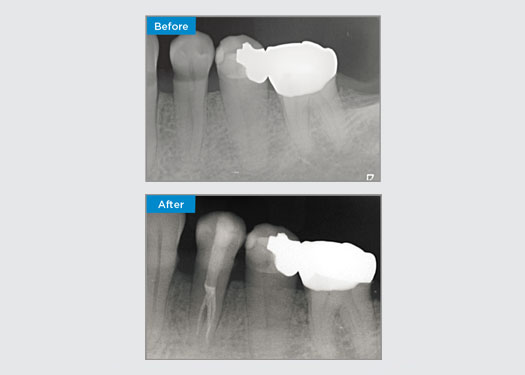

Este paciente presenta una restauración rota en la cara distal-oclusal del diente 46. La restauración existente del diente se extiende muy profundamente y cerca de la cámara pulpar. Dado el gran tamaño de la restauración, era muy probable que, si simplemente reemplazáramos la restauración por otra restauración directa, el resultado fuera el mismo, y se rompiera la restauración bajo las cargas oclusales a las que están sometidos el diente y la restauración. Por eso, se recomienda una opción indirecta para el diente. Como el tercio mesial del diente no se veía demasiado afectado y quedaba una estructura dental sana sustancial, pudimos preservarlo y ser mínimamente invasivos restaurando el diente con una restauración indirecta utilizando el sistema CEREC

Dr. Sahil Soni, Queensland, Australia